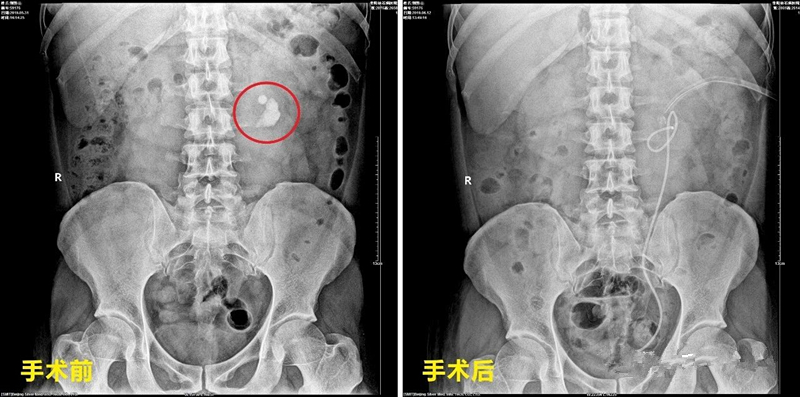

▲郭先生术前术后X光对比图

短短几天之后,郭先生便可下床活动,7天后,恢复良好的他在医护人员的陪同下,再次进入手术室,迎来与肾下盏结石的最终“战役”。主治医生耗时35分钟,通过“ 左侧输尿管软镜钬激光碎石术 ”,将这枚1.2x1.0cm的黄色结石彻底粉碎。